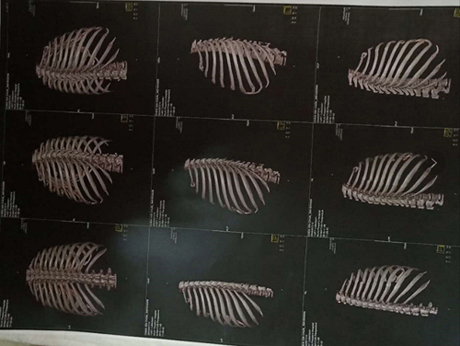

我叫陈新春,女,1968年3月出生,小学文化程度,江苏省盐城市射阳县人。2017年11月3日,在江苏省常州市新北区文化广场工地,八号楼二楼清理施工垃圾。因安全措施不到位,从6米高空施工洞坠入,造成颈椎骨折,脊柱骨折,腰椎L1一6横突骨折,腰椎右侧横突骨折,右侧髋臼,股骨头骨折装钢板,盆骨右侧L1一5骨折,左侧L1一5骨折,双侧耻骨折,左侧髋臼可疑骨折,腰椎至骨盆除左侧髋臼可疑骨折,全部骨折,外阴跌撕,胸椎骨折,内骨粉质性骨折,内骨右侧横突L1一4骨折,内骨左侧3一7两处骨折,右侧肋骨L1一10骨折,右侧肋骨后缘3一7两处骨折,左侧肋骨1.2.3.5.6.7.10骨折,后缘肩往下1一4两处骨折,左肩袖损伤肌健骨折;左冈上肌损伤,左肱骨因血液不流通,左肱骨长一个小圆形囊肿,腹部闭合性损伤,全身多处软组织损伤;双侧微量气胸,肝挫伤出血,脾挫伤出血,左肾挫伤出血,右肾上泉挫伤伴血肿,右肺上叶及两肺下叶挫伤出血,内腹部都挫伤出血。

这里所提供的几张片子拍出的颈椎骨折,腰椎横突骨,脊柱骨折,左侧盆骨骨折,内骨粉质性骨折,内骨左侧3一7两处骨折胸椎骨折,报告单都没有。报告单上有50根骨折包括两处有的,只出三分之一的骨折。常州市武进人民医院涉嫌隐瞒我的伤情,进手术室开刀涉嫌隐瞒了主要骨折的片子,去要片子不给;补出院小结,补两次,颈椎骨折,腰椎骨折,胸椎骨折,内骨粉质性骨折还不肯补。